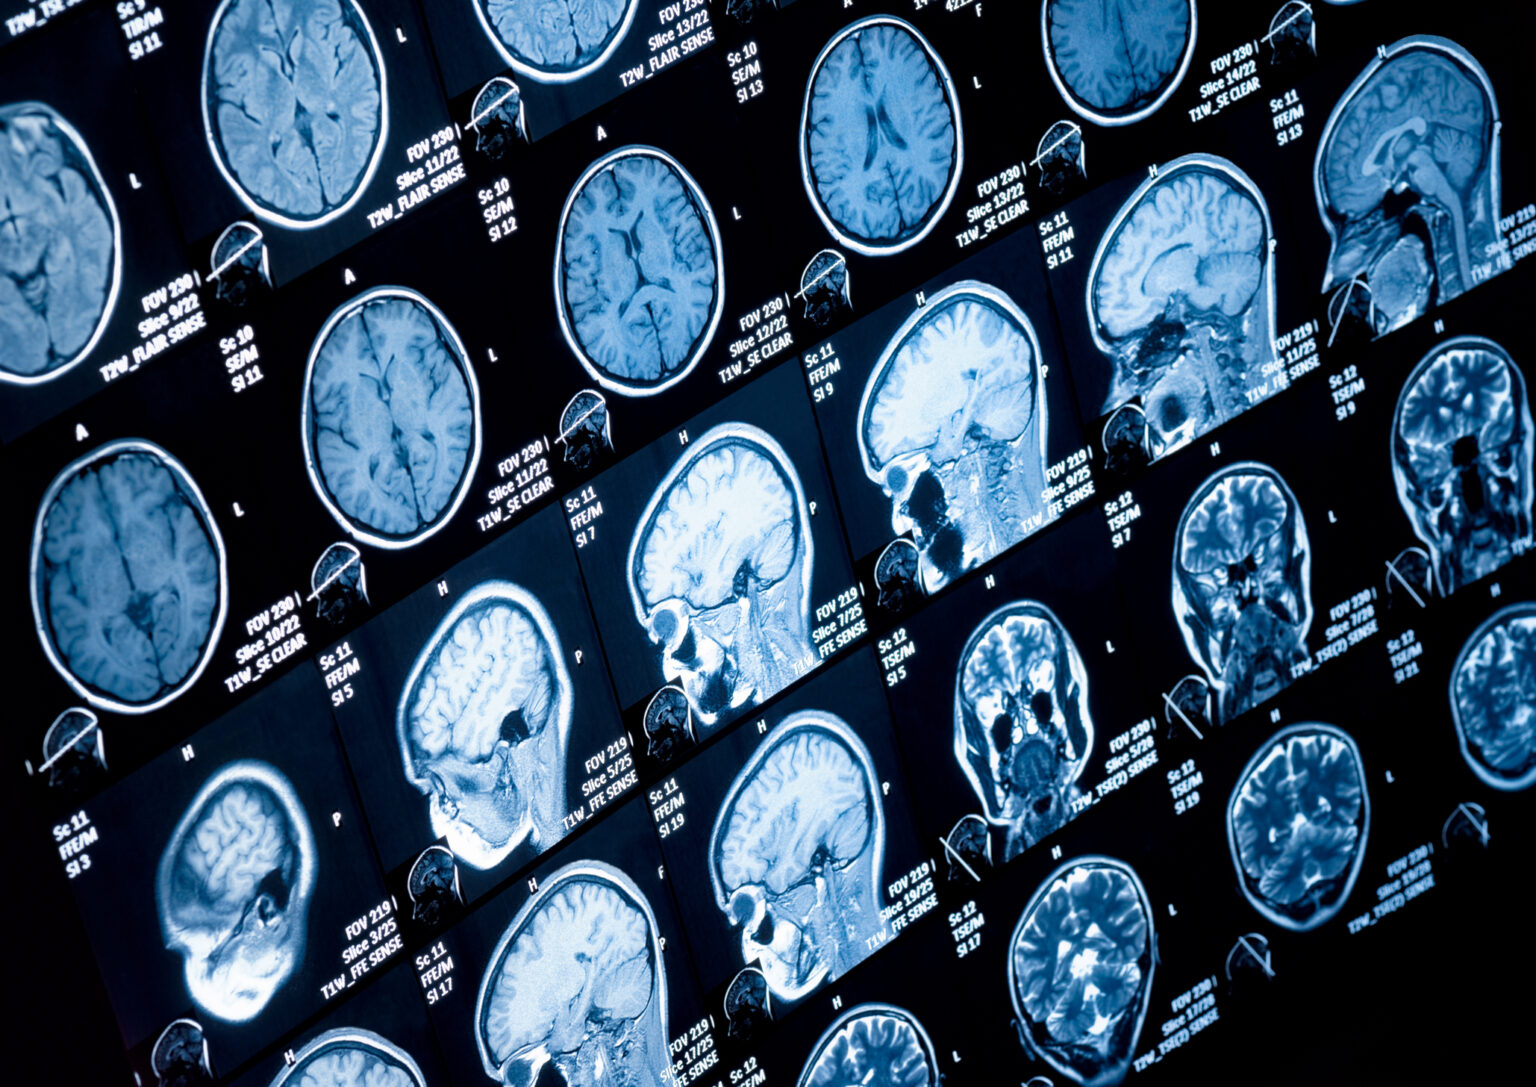

Brain white matter abnormalities affect cognition and impact Alzheimer’s disease development: study

Data from more than 4,000 participants reveals link between brain structure and cognitive decline.